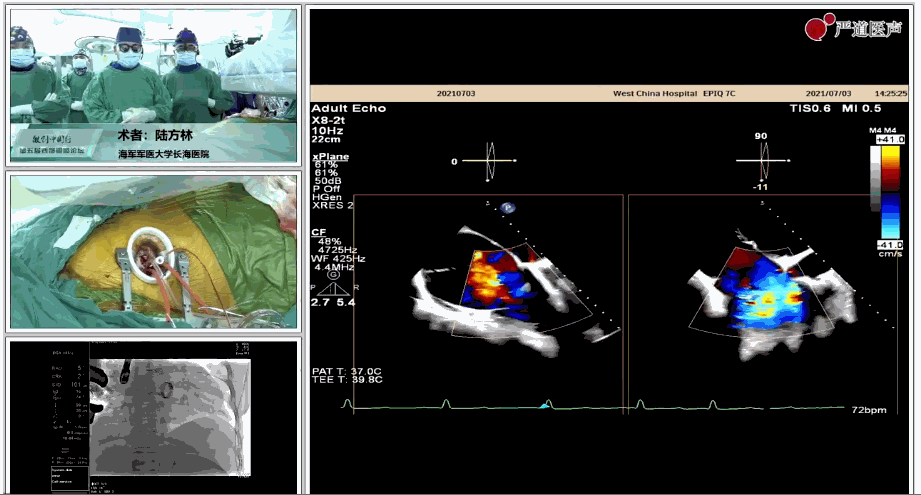

7月3日下午,海軍軍醫(yī)大學(xué)附屬上海長(zhǎng)海醫(yī)院心血管外科徐志云、陸方林團(tuán)隊(duì)在論壇中分享了經(jīng)導(dǎo)管三尖瓣置換術(shù)(LuX-Valve®)的手術(shù)直播演示。線下會(huì)議由陶涼教授、潘文志教授、喬晨暉教授共同參與討論和臨床分享。

陸方林教授分享的是一例極重度三尖瓣返流的患者采用健世科技(LuX-Valve®)經(jīng)導(dǎo)管三尖瓣置換系統(tǒng)進(jìn)行的手術(shù)直播演示。此例患者為69歲女性,入院前17年行二尖瓣機(jī)械瓣置換術(shù),術(shù)后長(zhǎng)期服用華法林抗凝,既往“2型糖尿病”病史5年,“雙下肢水腫”3年。3個(gè)月前患者出現(xiàn)腹脹、雙下肢水腫,伴活動(dòng)后暈厥,伴黃疽、皮膚濕癢、牙齦出血,癥狀持續(xù)加重,遂入院治療。入院后行心臟CT、心臟超聲檢查,提示:“三尖瓣關(guān)閉不全(極重度),二尖瓣置換術(shù)后,心功能III級(jí)”。徐志云、陸方林微創(chuàng)三尖瓣置換團(tuán)隊(duì)對(duì)該患者的病情進(jìn)行了充分的評(píng)估和討論。由于患者有開(kāi)胸二尖瓣置換手術(shù)史,且病史時(shí)間長(zhǎng),同時(shí)存在相關(guān)合并癥,傳統(tǒng)外科手術(shù)風(fēng)險(xiǎn)極高(STS評(píng)分:8.315%),最終決定采用三尖瓣LuX-Valve®瓣膜系統(tǒng)對(duì)患者進(jìn)行治療。

▲術(shù)中食道超聲顯示三尖瓣極重度返流